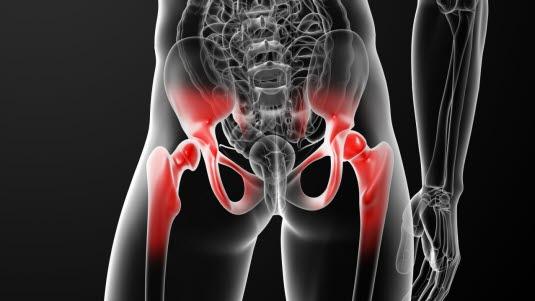

I pubertetsårene kan en sykdom oppstå i vekstsonen til lårbeinet, en såkalt epifysiolyse. Toppen av hoftekula (lårbeinshodet), som befinner seg ovenfor vekstsonen, begynner å gli bakover og nedover.

I de lange rørknoklene i beina og armene finnes vekstsoner eller vekstskiver der lengdeveksten i knoklene foregår. Denne vekstsonen betegnes på fagspråket for epifysen, og den befinner seg nær enden på et bein, det vil si nær leddet. I hoftekula på lårbeinet finnes en slik epifyseskive. I pubertetsårene kan vekstskiven svekkes og løsne fra benet, en såkalt epifysiolyse. Toppen av hoftekula (lårbeinshodet), som befinner seg ovenfor vekstsonen, begynner å gli bakover og nedover. Situasjonen kan sammenlignes med en softis som glir av kjeksen. Tilstanden må korrigeres raskt for å unngå livslange hofteplager.